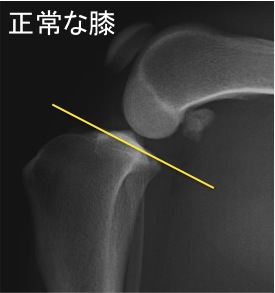

ではなぜ前十字靭帯は断裂してしまうのでしょうか? それはわんちゃんの脛骨の形に特徴があるからだと言われています。 わんちゃんの脛骨は正常でも下のレントゲンのように斜めに傾いています。

*

このため上から力がかかると脛骨が前に出る力が発生します。